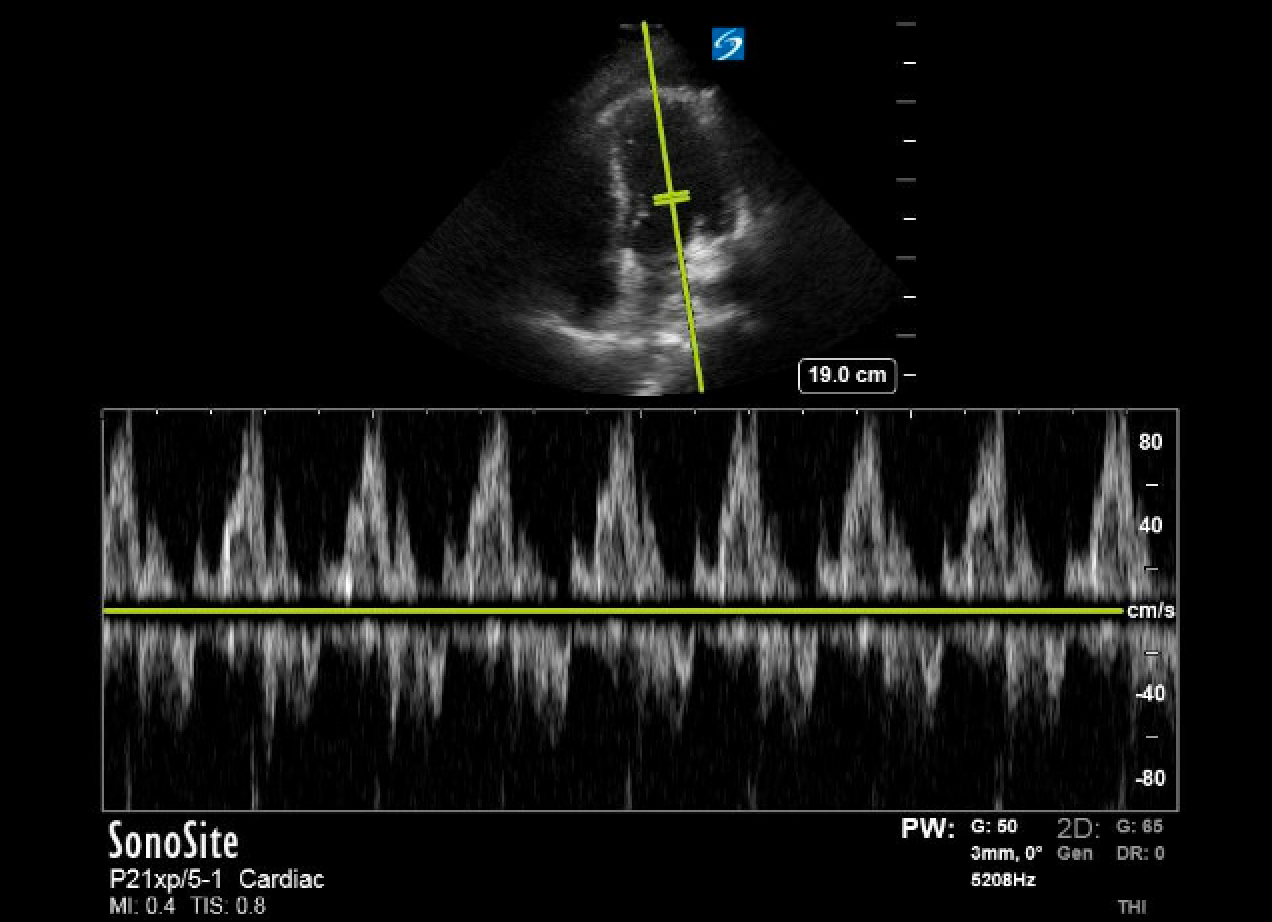

ACEP Now: Feb Digital 01-DLimited point-of-care ultrasound (POCUS) demonstrated a pericardial effusion and a large left-sided pleural effusion. The heart was inferiorly displaced; the apical four-chamber view was obtainable with the probe positioned superior to the umbilicus. Evidence of cardiac tamponade was present, including right ventricular diastolic collapse and greater than 25 percent mitral valve inflow velocity variation (see figure 1). Thoracic surgery requested CT imaging to evaluate for surgical complication; however, the patient was too unstable.

Figure 1. (A) Mitral valve inflow (MVI) velocity variation measured prior to chest thoracostomy. In this patient, MVI velocity variation is elevated at 37.5 percent, which is indicative of tamponade physiology. (B) Normalized MVI velocity variation after chest tube thoracostomy.

In normal physiology, inspiration leads to increased negative intrathoracic pressure, allowing for increased preload of both ventricles. In tamponade, there is increased interventricular dependence, and the septum bows more dramatically into the left ventricle during inspiration, decreasing the amount of blood filling the left heart. This is measured with sonography by placing the pulse wave Doppler gate in the left ventricular space at the opening of the mitral valve leaflets in an apical four chamber view, thereby measuring the speed of left ventricular filling. Mitral valve inflow velocity variability greater than 25 percent is characteristic of cardiac tamponade, as natural interventricular dependence throughout the respiratory cycle is increased and can be thought of as the sonographic equivalent of pulsus paradoxus.1